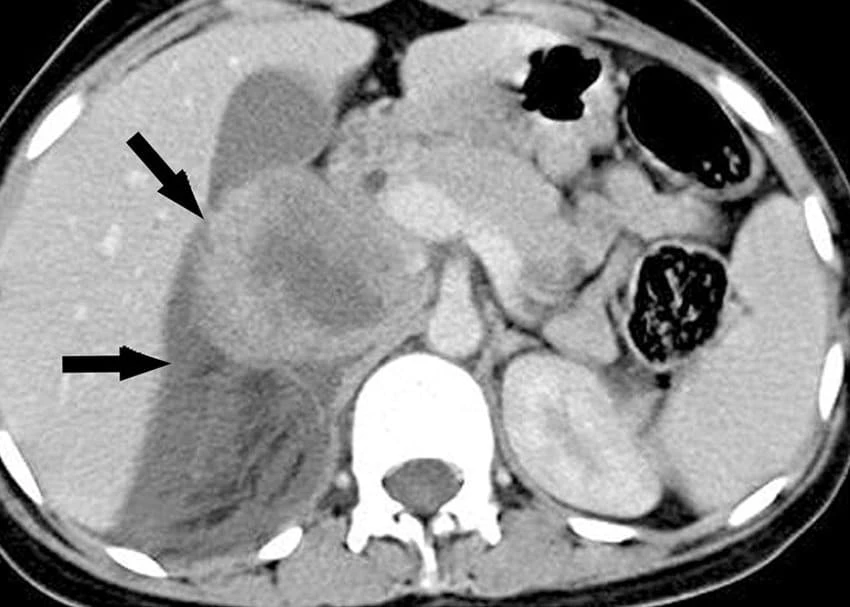

- Chẩn đoán hình ảnh: Các kỹ thuật chẩn đoán hình ảnh công nghệ cao như CT scan, MRI, PET giúp phát hiện và tầm soát các khối u với độ chính xác cao.